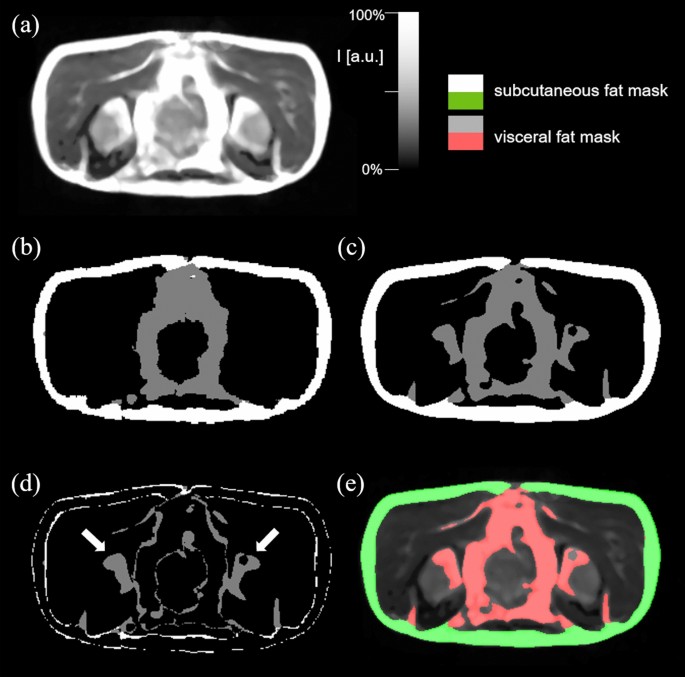

For both validation and test data, the average performance metrics are summarized in Table 1. The neural network was able to generate the segmentations at an average pixel error of 2% for SAT and 4% for VAT, respectively, in the ALS group of the validation set, while an average error below 1% for both fat compartments was achieved in the control group of the validation set. Similar performance was achieved on the test data with an average error below 3.5% in both groups. Dice similarity coefficients in the test data achieved 0.87 for SAT and 0.68 for the VAT compartment. Figure 1 shows the comparison of the segmentation performed on a single plane MR image from a control test dataset (Fig. 1a) by the reference method (Fig. 1b) and CNN (Fig. 1c), in addition visualized as a difference image (Fig. 1d); differences appear in bones and at the edges of structures suggesting that in comparison to the reference technique the neural networks tend to a smoothed segmentation without pixelated edges. The overlay of predicted SAT and VAT compartments on the original MR image is shown in Fig. 1e.

Prediction results from a test dataset from a control. (a) Original transversal MRI single plane image. (b) Reference segmentation mask. (c) Predicted label map. (d) Difference image between reference and predicted segmentation with arrows indicating major differences in prediction of VAT in hip bones. (e) Predicted segmented mask overlaid on original MR image.